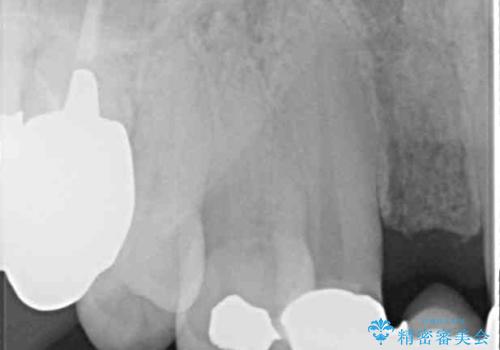

- ブリッジと歯肉の隙間にものが挟まったり空気が抜けたり、歯肉ラインの黒い縁が目立ってしまったりと、前歯のブリッジの作り直しを希望して来院された患者様です。

自然な仕上がりとするため、金属を使用しないオールセラミックブリッジにより補綴治療を行うこととしました。